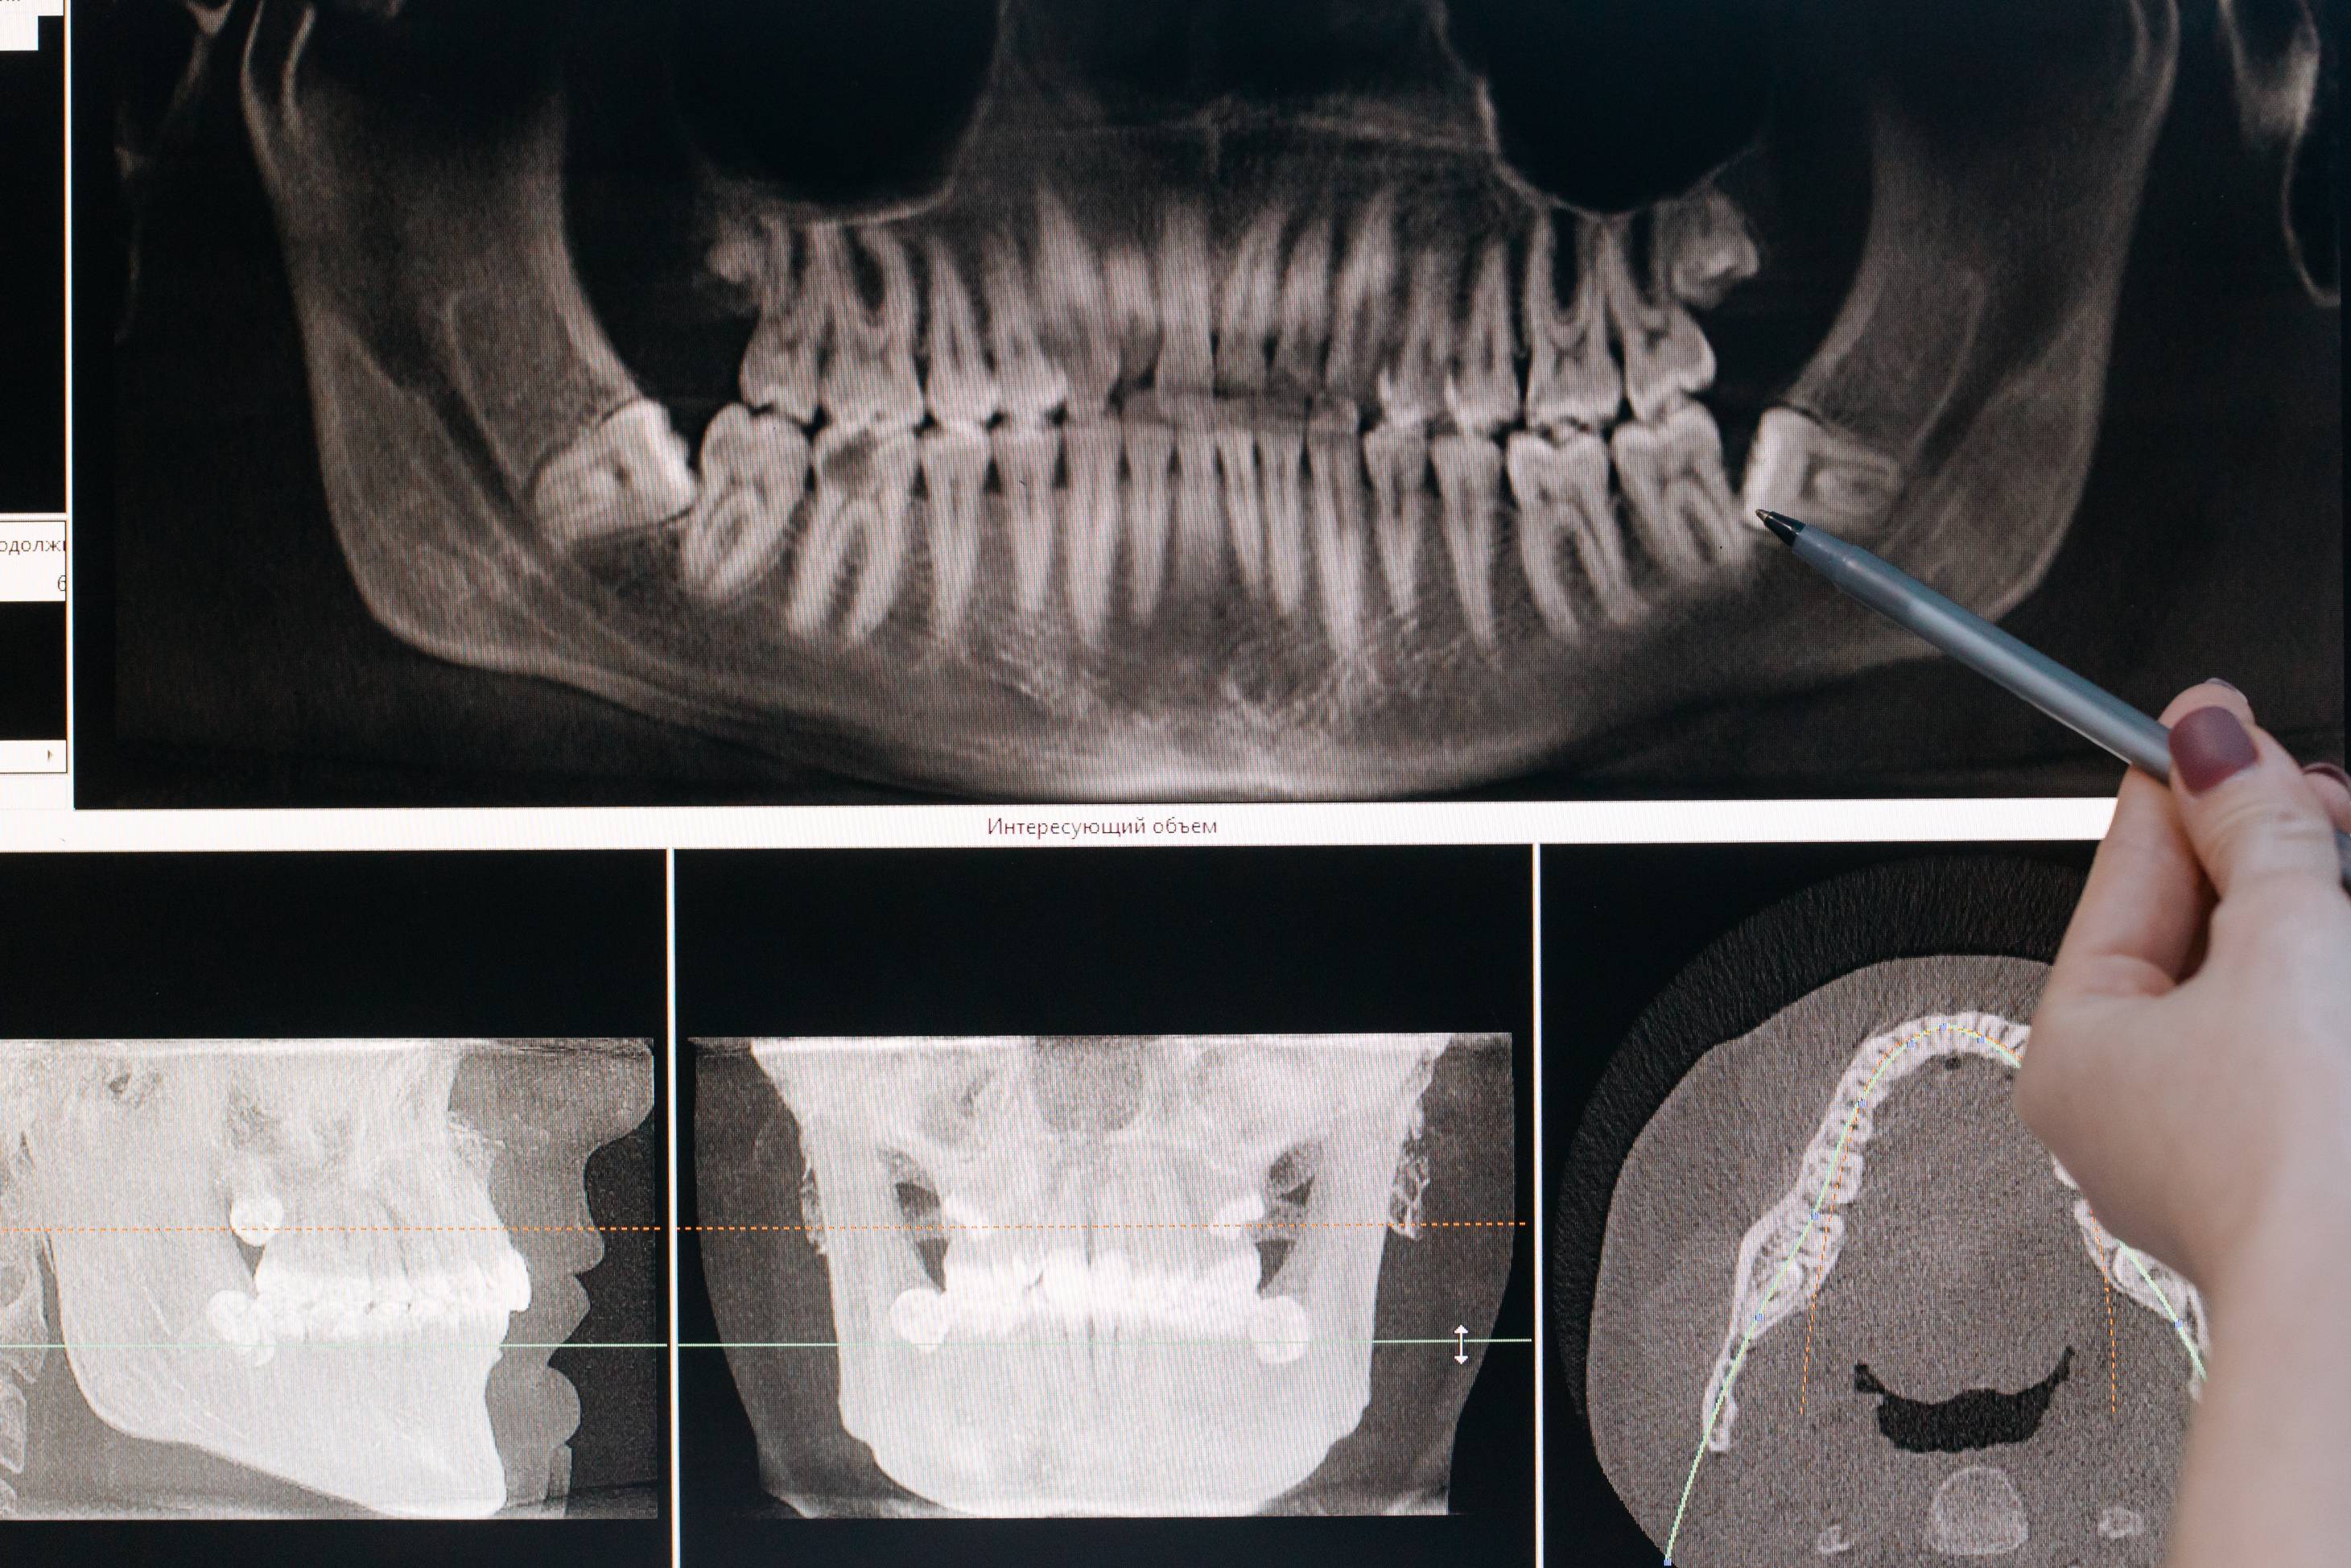

Traditional X-rays use a form of radiation to capture images of your teeth and oral structures, but the process can be time-consuming. They also expose you to more radiation than necessary. With digital X-rays, our dentist can capture images immediately using a small sensor placed in your mouth. This sensor is attached to a computer screen that allows us to view the images instantly.

The images are more precise and can also be sent electronically for further diagnosis or treatment. Our dentist can review the images with you and discuss any necessary procedures.

The digital images help our dentist identify problem areas in the mouth that wouldn’t be as visible during a visual exam or when using traditional X-rays. For example, the small sensor that captures these images can help the dentist see cavities between teeth. In addition, our dentist can adjust the images to help highlight specific areas of the mouth.